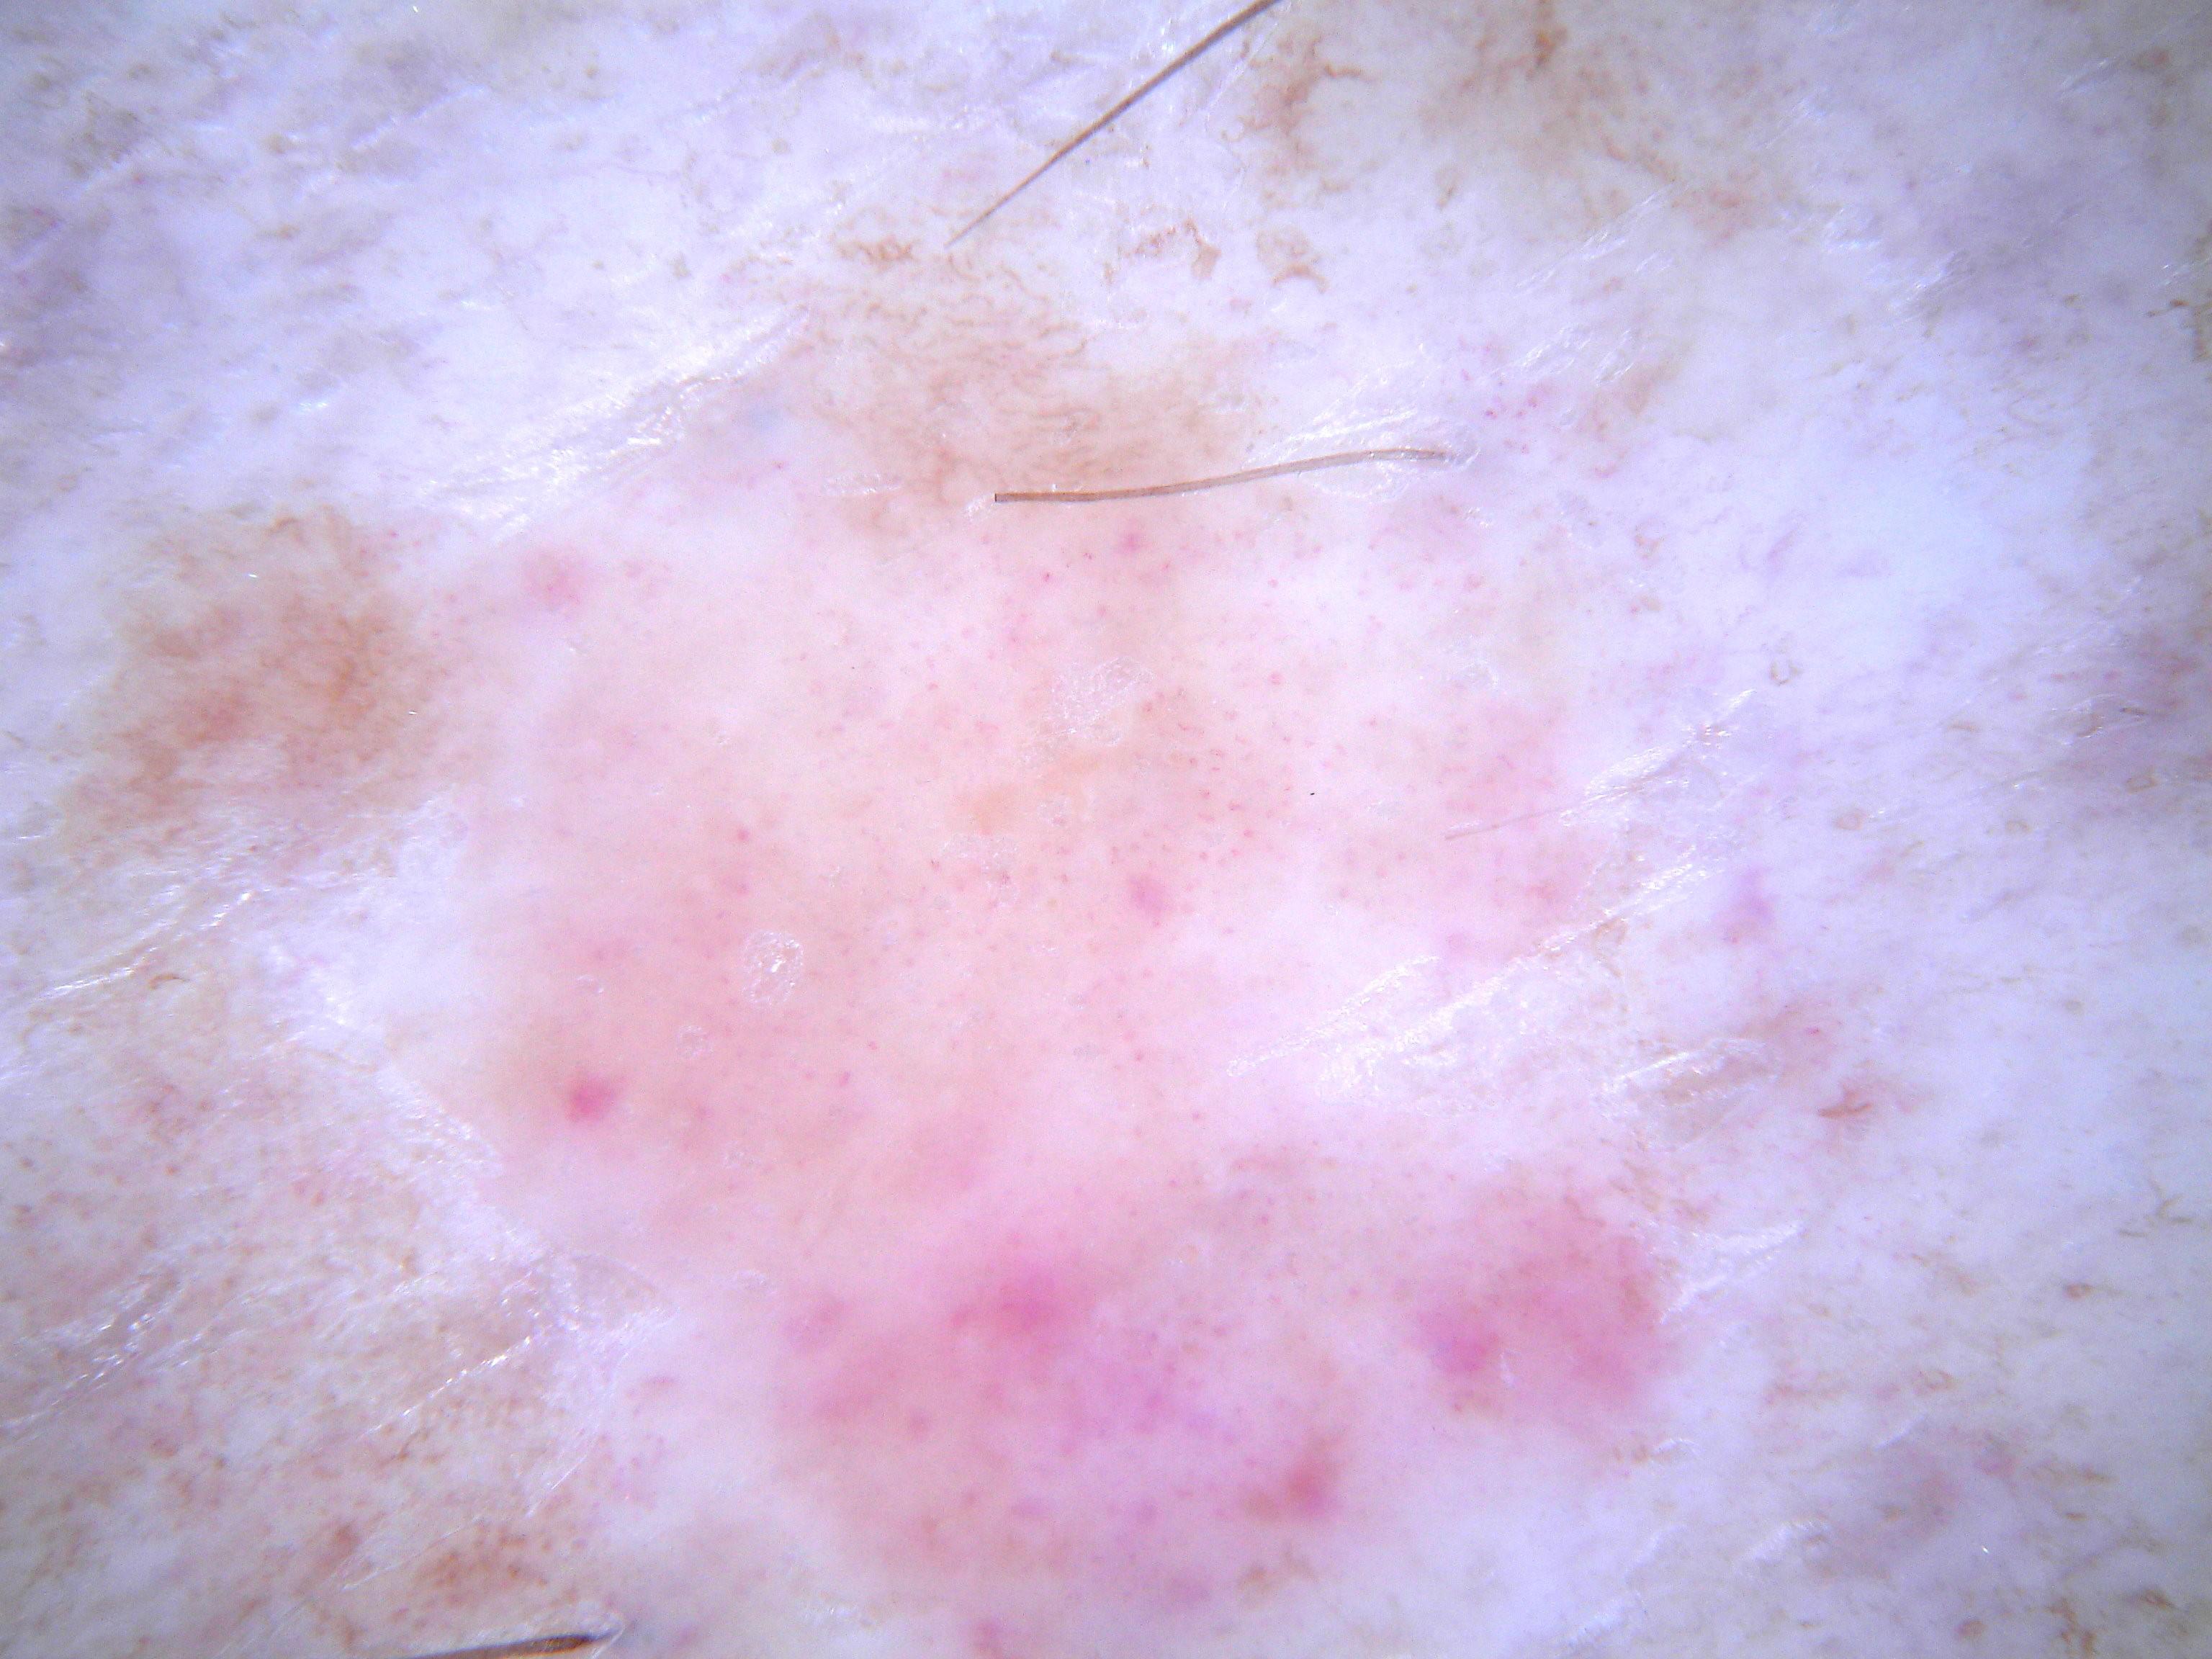

{

"age_approx": 45,

"anatom_site_general": "upper extremity",

"concomitant_biopsy": true,

"dermoscopic_type": "contact polarized",

"diagnosis_1": "Malignant",

"diagnosis_2": "Malignant adnexal epithelial proliferations - Follicular",

"diagnosis_3": "Basal cell carcinoma",

"diagnosis_confirm_type": "histopathology",

"family_hx_mm": true,

"image_type": "dermoscopic",

"melanocytic": false,

"patient_id": "IP_9544667",

"personal_hx_mm": false,

"sex": "male"

}